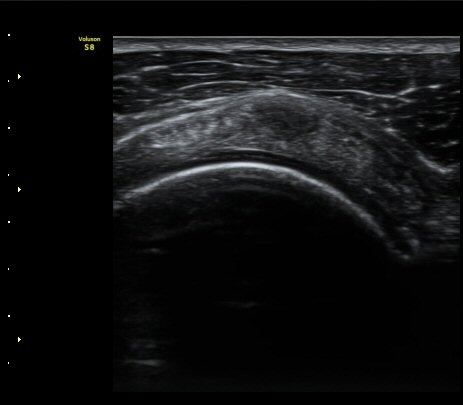

À̵Π¹Ú±Ù°Ç Ⱦ´Ü¸é°Ë»ç¿¡¼­ ƯÀÌ ¼Ò°ßÀ» º¸ÀÌÁö ¾ÊÀ½(»çÁø 1)